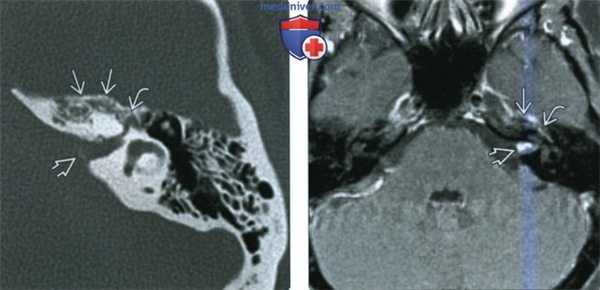

(Слева) При аксиальной КТ в костном окне у пациента с правосторонним параличом лицевого нерва визуализируется маленькая ВМЛН в ямке коленчатого ганглия. Обратите внимание на точечные костные очаги в структуре, которые позволяют отличить ВМЛН от шванномы лицевого нерва, которая также возникает преимущественно в ямке коленчатого ганглия.

(Справа) При аксиальной МРТ Т1 С+ FS у этого же пациента определяется ВМЛН, накапливающая контраст, в области коленчатого ганглия. Область точечных кальцинатов выглядит как гипоинтенсивный фокус.

(Слева) При аксиальной КТ правой височной кости определяется среднеразмерная ВМЛН в ямке коленчатого ганглия, распространяющаяся вдоль передневнутренней поверхности височной кости ВМЛН имеет типичную форму полумесяца, огибающего улитку с внутренней стороны на передней поверхности височной кости.

(Справа) При аксиальной МРТ Т1С+ у этого же пациента определяется диффузное контрастное усиление ВМЛН в ямке коленчатого ганглия, огибающее улитку вдоль передневнутренней поверхности височной кости.

(Слева) При аксиальной КТ в костном окне в передневнутренних отделах височной кости и в кости вокруг ямки коленчатого ганглия определяется ВМЛН. В ВСК также визуализируются едва различимые очаги высокой плотности.

(Справа) При аксиальной MPT Т1 C+ FS y этого же пациента в передневнутренних отделах височной кости вокруг коленчатого ганглия и в ВСК определяется венозная мальформация, накапливающая контраст. Часть ВМЛН в ВСК обусловлена распространением вдоль лабиринтного сегмента ЧН VII (не показан).